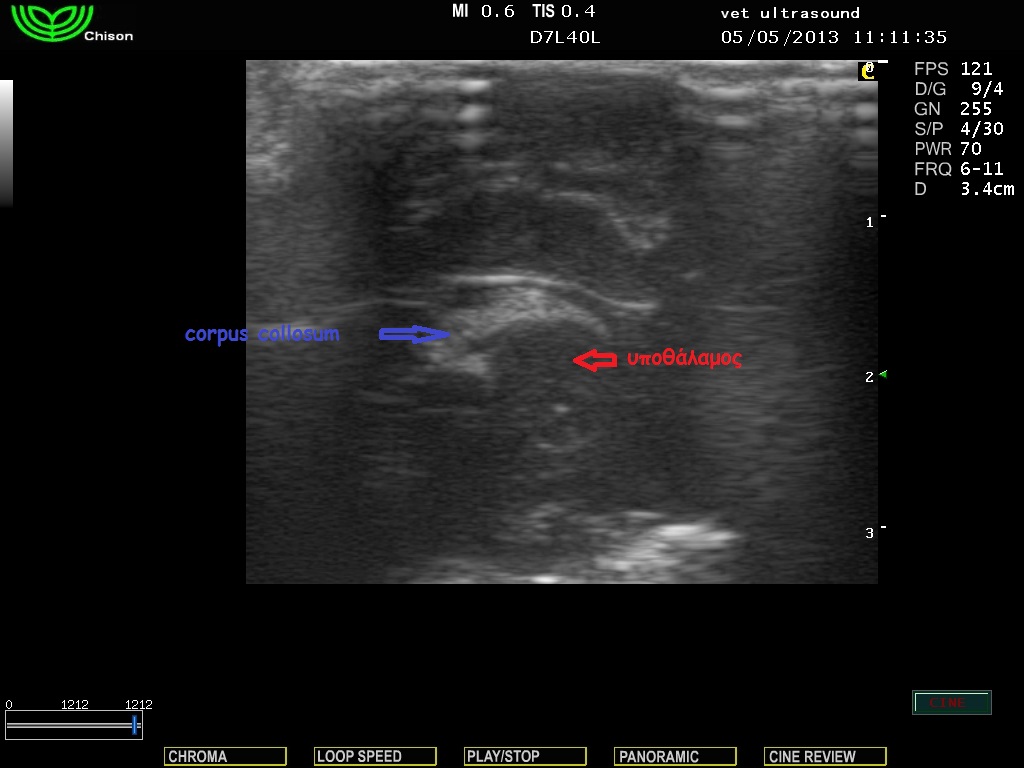

Στην κλινική εξέταση δεν παρατηρήθηκαν αλλοιώσεις στην νευρολογική εξέταση των εγκεφαλικών συζυγιών και των νωτιαίων νεύρων. Υπήρχε μία μικρή απόκλιση των οφθαλμών από τον κεντρικό άξονα και για τον λόγο αυτό είχε θορυβηθεί ο ιδιοκτήτης. Δεν είχε επέλθει οστεοποίηση των συναρθρώσεων των οστών του κρανίου, οπότε η υπερηχοτομογραφική εξέταση ήταν εφικτή διαμέσου της συνάρθρωσης των βρεγματικών με τα μετωπιαία οστά. Δεν υπήρχε διάταση των πλάγιων κοιλιών του εγκεφάλου και έτσι το ενδεχόμενο του υδροκέφαλου αποκλείστηκε.

Επιμήκης τομή του εγκεφάλου.